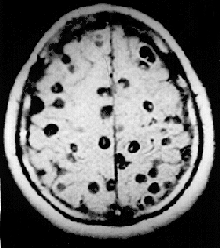

- Neurocysticercosis (NCC): is an infection of the brain or spinal cord caused by the larval stage of the pork tapeworm, Taenia solium. NCC is the most common helminthic (parasitic worm) infestation of the central nervous system worldwide. Humans develop cysticercosis when they ingest eggs of the pork tapeworm via contact with contaminated fecal matter or eating infected vegetables or undercooked pork.[37] "While cysticercosis is endemic in Latin America, it is an emerging disease with increased prevalence in the United States."[38] "The rate of depression in those with neurocysticercosis is higher than in the general population."[39]